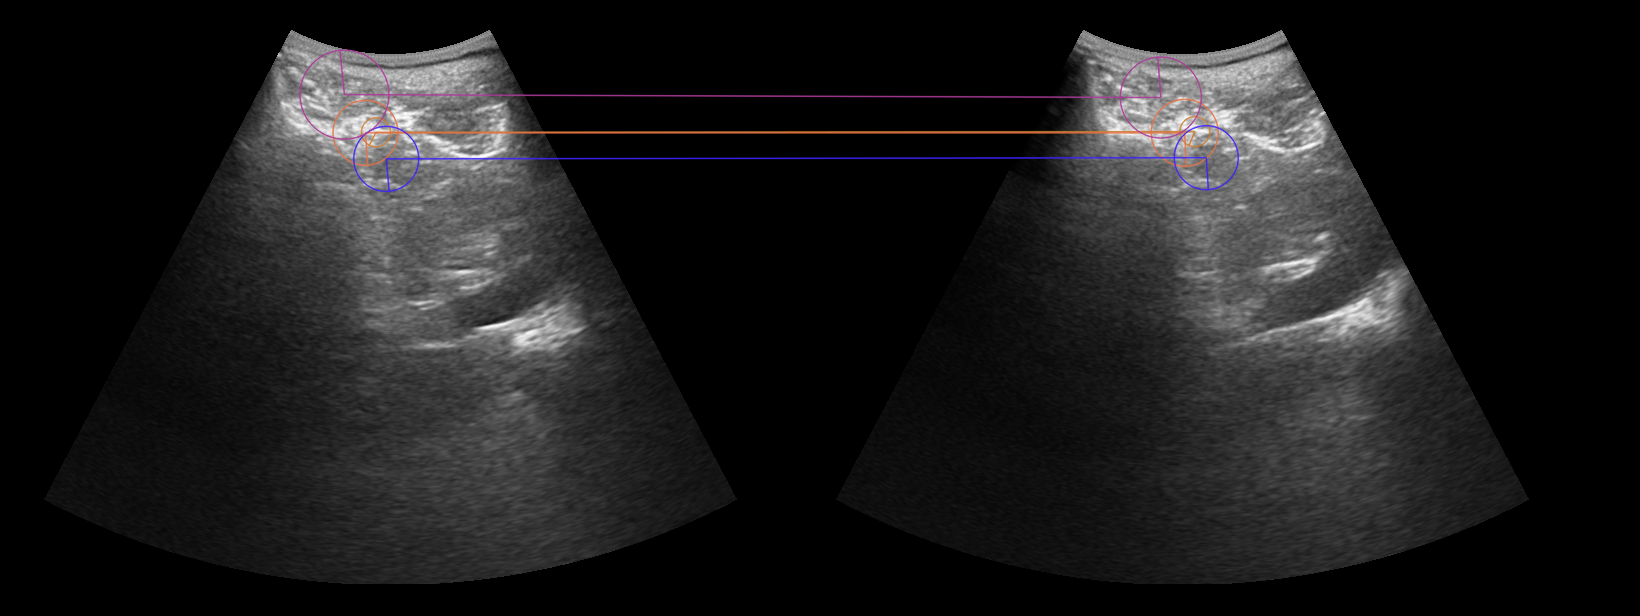

- Develop a system to use calibrated, tracked ultrasound to intra-operatively track and visualize pre-operatively defined neurosurgical targets.

- Challenges: 2D-3D registration, intra-operative deformation and missing tissue, inter-modal image registration.

- Data preparation: ultrasound image and probe tracking information (PLUS system).

- Code development: pre-op to intra-op image matching using scale-invariant features.